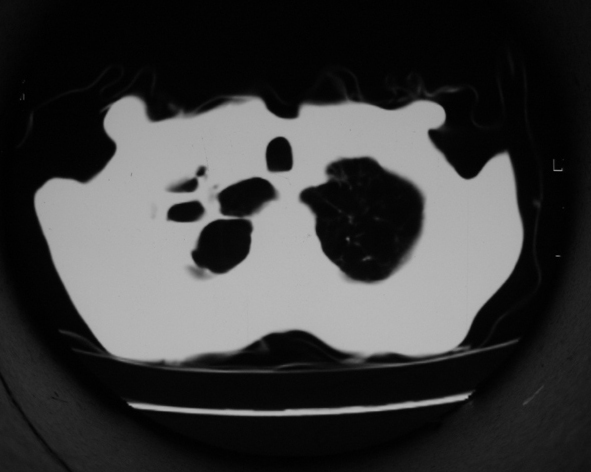

男53岁,咳嗽气短,以往身体健康.

1.右肺上叶干酪性肺炎,2。肺气肿,肺大泡

支持右上肺继发性肺结核并干酪性肺炎,右肺大泡,左肺代偿性气肿。